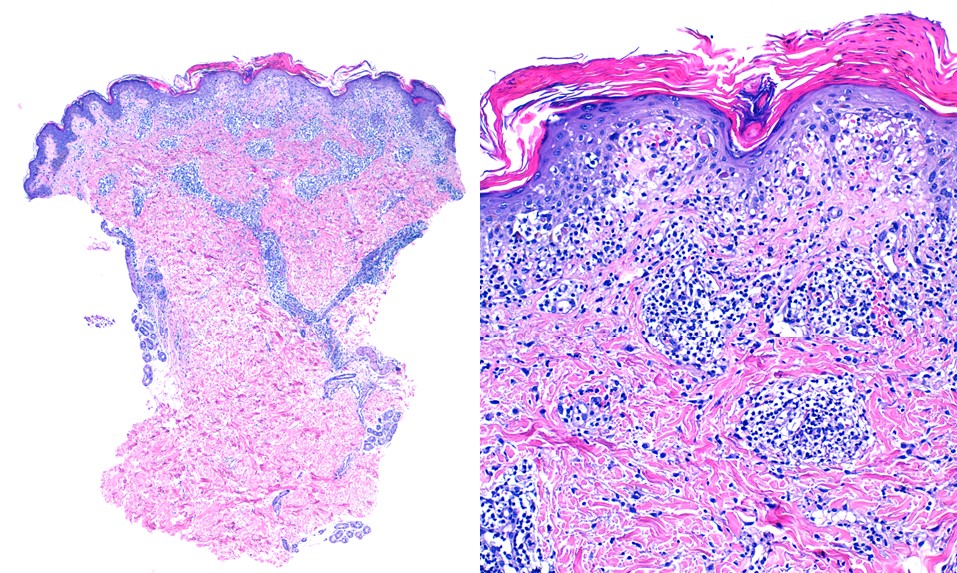

Anatomía patológica de la PLEVA

Presencia de infiltrados inflamatorios linfocitarios perivasculares en la dermis superficial, con exocitosis epidérmica de estos linfocitos y escamas paraqueratósicas con acumulación de células inflamatorias entre las diferentes capas.

Punch cutáneo de biopsia diagnóstica de PLEVA